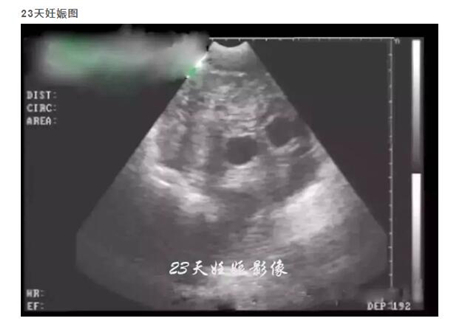

20天孕期左右的母猪,即可进行B超测孕,但由于羊水太少,图像不好判断,准确度也会因检测人员经验因素有所影响,容易造成误判,而且检查时间长,耗费人力。